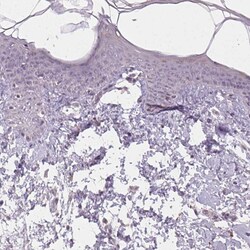

- Immunohistochemical analysis of NKG2E in human skin using NKG2E Polyclonal Antibody (Product # PA5-64033) shows no positivity in squamous epithelial cells as expected.